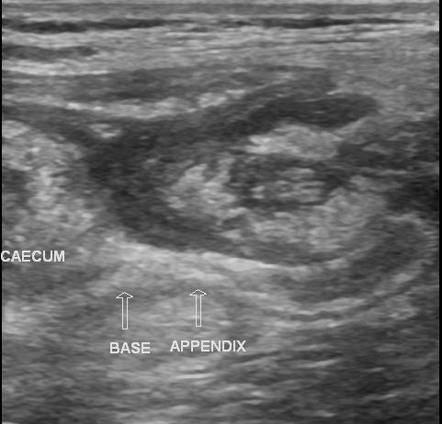

Abdominal Ultrasound

Interpretation

Appendicitis suspected.